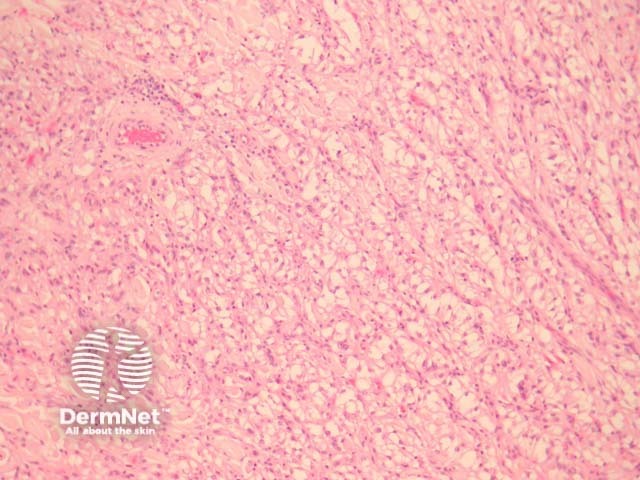

Sections show a discrete mass in the dermis (figure 1). The tumour is composed of epithelioid cells with clear to eosinophilic cytoplasm and round to oval nuclei with obvious nucleoli (figure 2-3). They frequently exhibit a nested or trabecular arrangement (figure 3).

Figure 1